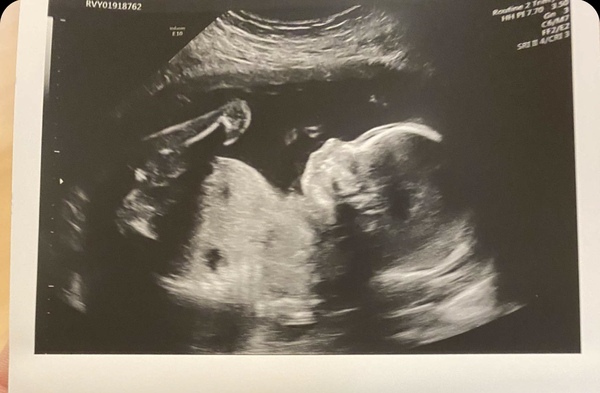

Had my 20 week scan today, was absolutely amazing nothing compared to any other scan I’ve had. Got to see lots of details and even the umbilical cord!!! Little man doing really well, got to see in depth detail of his arms and legs and he was in a great position! Growing at perfect rate

@Firstmummytobe that's such a clear pic! I can't believe how big the baby is compared to the 12 weeks scan.

@Firstmummytobe wow that is such a clear picture! Did they show you everything they were doing? Mine is this coming Wednesday, hopefully baby behaves and we can find out the gender 😊